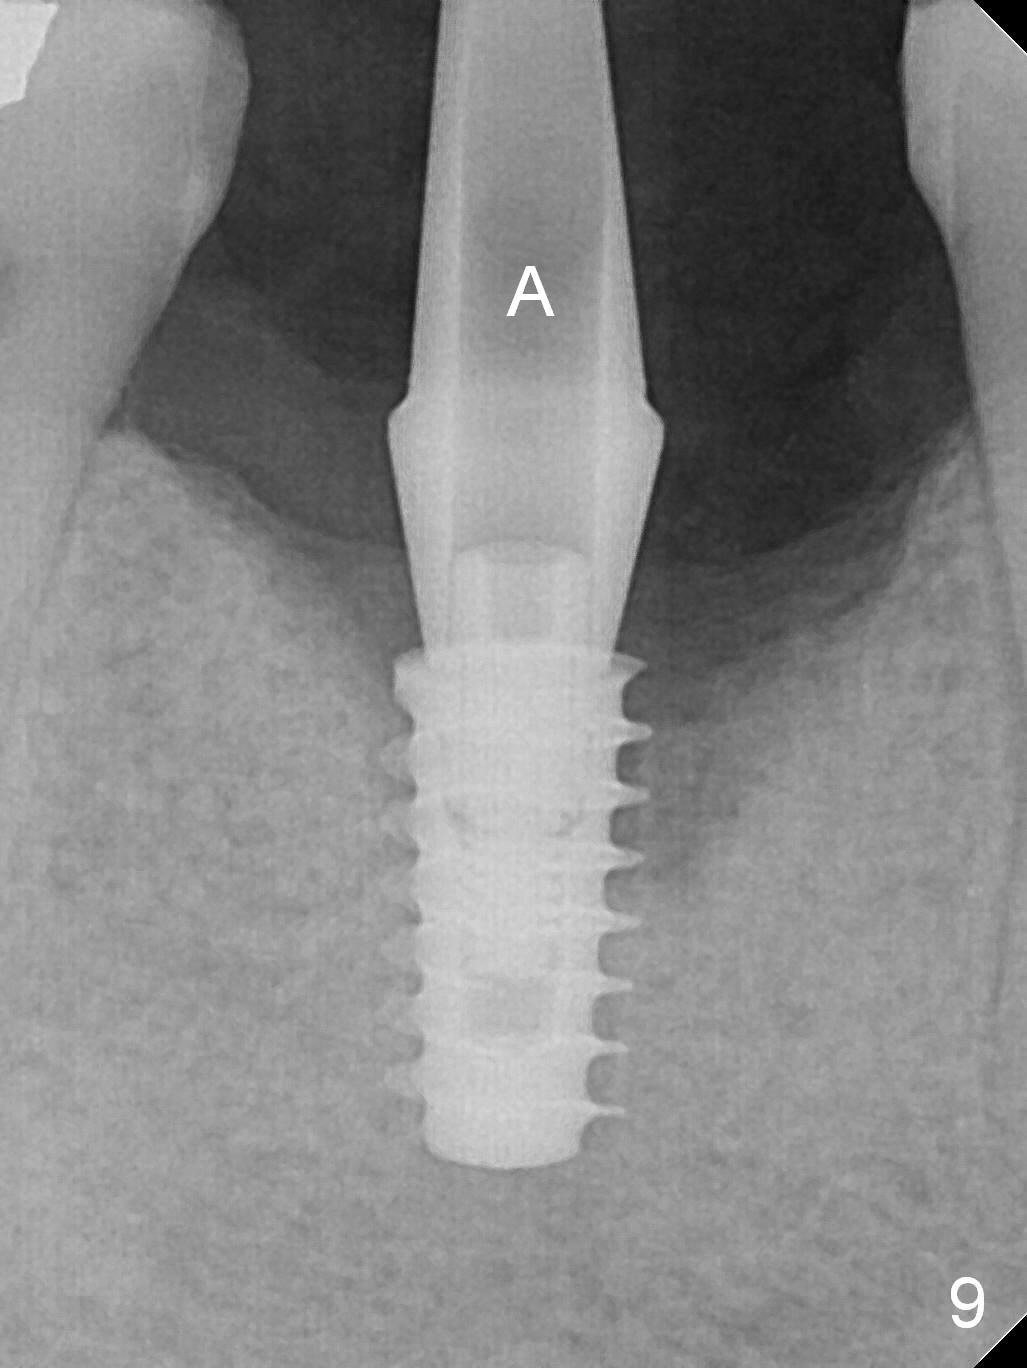

A 49-year-old man develops acute abscess of the lower right quadrant (Fig.3-5) secondary to periimplantitis at #30 (Fig.1,2,6). The latter is probably due to buccal placement (Fig.6 (*: buccal plate)). After removal of the infected implant, an osteotomy is established as lingual as possible using single drill modality (Fig.7 (4.3 mm Magic Drill after 1.6 mm pilot drill and Marking Bur, then Final Drill). With the single drill, the osteotomy does not shift buccally in spite of the lower buccal plate. A 5x9 mm IBS implant is placed lingually as planned (Fig.8 (>40 Ncm)), followed by an angled abutment (5 mm x 15° (4 mm)) (Fig.9 A). The buccal gap is filled with autogenous bone, allograft (.5-1.5 mm) and Osteogen (Fig.10 *), covered by resorbable and non-resorbable membranes. After suturing, periodontal dressing is applied.